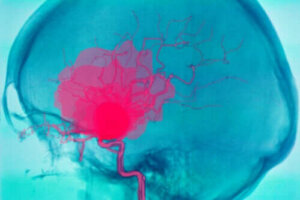

En intracerebral blødning, som vi nevnte innledningsvis, er blødning som oppstår inne i hjernen. Det forårsaker vanligvis plutselige nevrologiske defekter og til og med koma.

Dette skyldes mangel på blodtilførsel til andre deler av hjernen, siden blodet ikke fortsetter reisen gjennom blodårene. Det er viktig å skille mellom intracerebral og intrakraniell blødning.

Intrakranielle blødninger, i tillegg til intracerebrale blødninger, inkluderer andre som forekommer inne i hodeskallen, men ikke i hjernens parenkym. For eksempel intraventrikulære, subaraknoidale, subdurale og epidurale blødninger.